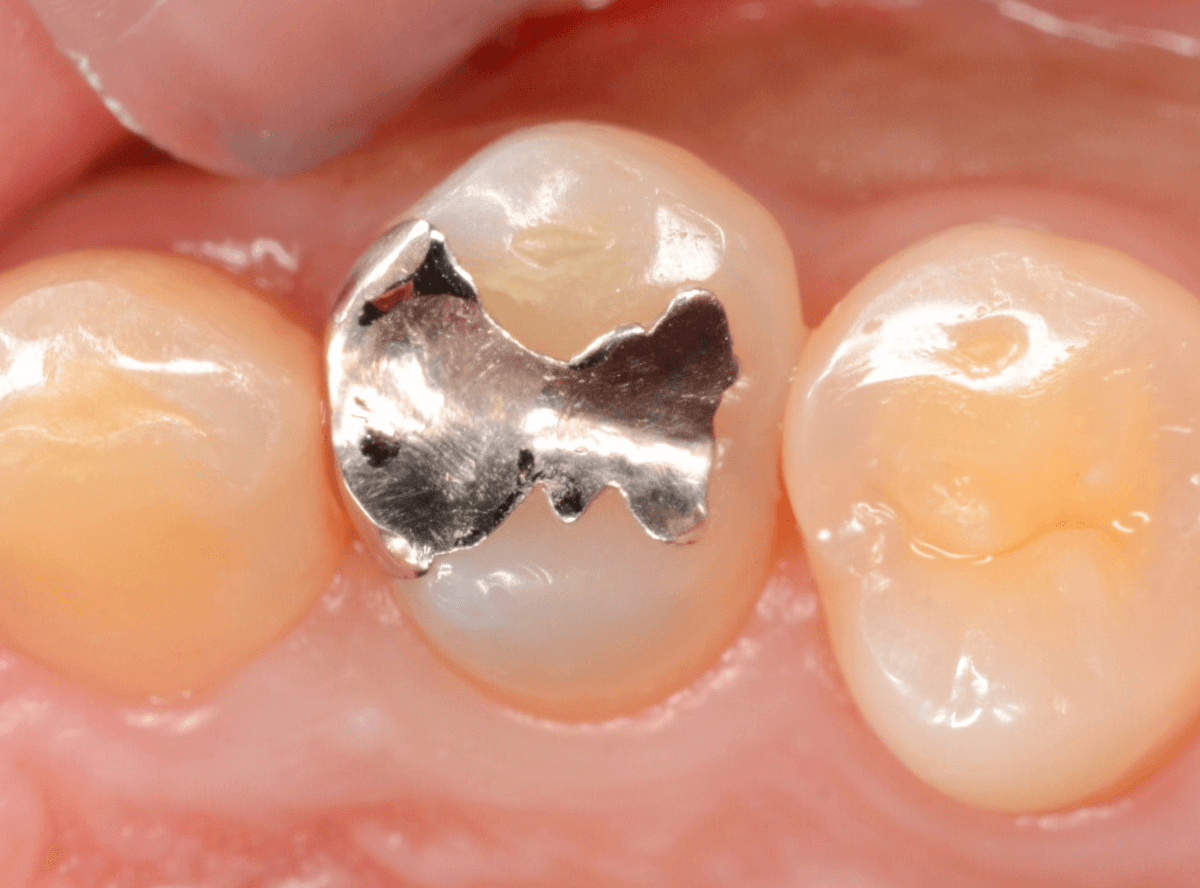

「下の奥歯の銀歯を白くしたい」というご希望の患者さんです。

メタル・インレーとメタル・クラウンが入っていますね。

まずは、奥のメタル・クラウンを外します。

メタル・コアが入っていますが、こちらも慎重に外して、中を調べていきます。

レントゲン写真では問題なさそうでしたが、メタルコアを除去すると、中は真っ黒でした。

このように、コアの中で虫歯が進行している場合もありますので、さし歯をやり直す際は、出来る限りコアも外して調べるようにしています。